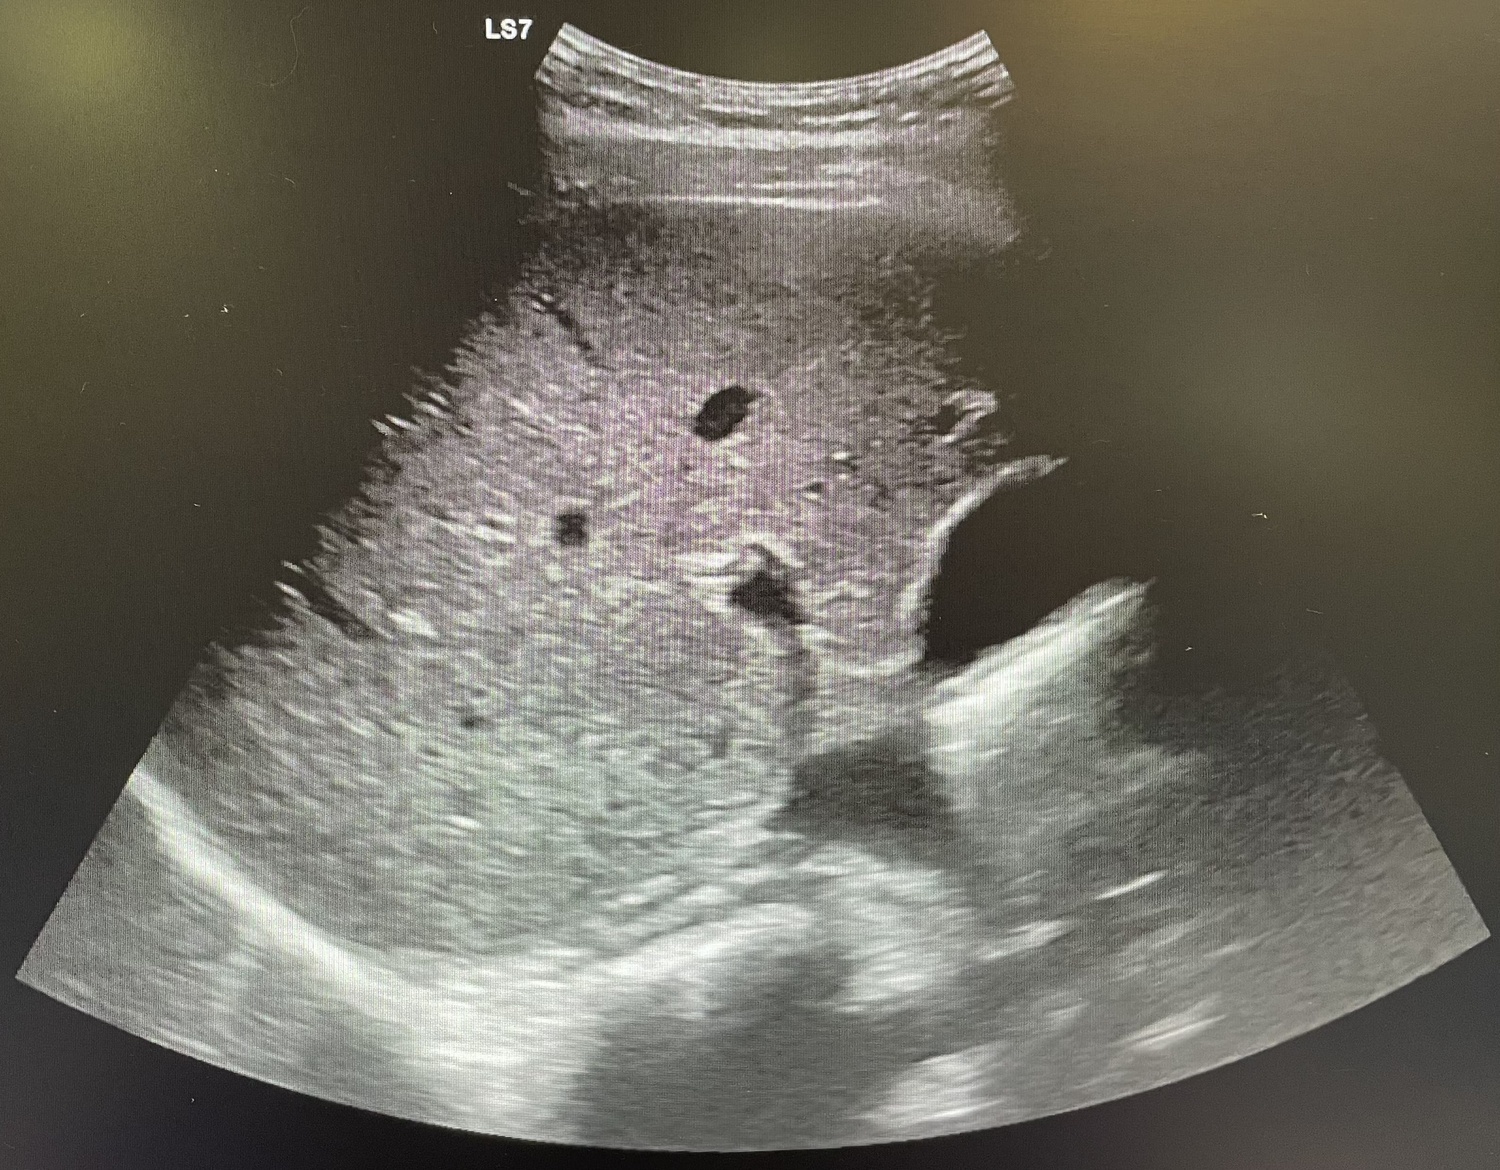

Se realiza analítica con aumento de reactantes de fase aguda (leucocitos 18.00 y PCR 108) y se indica ecografía abdominal que resulta no concluyente, por lo que se procede a alta.

Al día siguiente vuelve con la misma sintomatología, el dolor no cede con analgesia habitual. En la exploración Blumberg claramente positivo, se solicita analítica (leucocitos 13.000 y PCR 127) y se repite ecografía de abdomen que se sigue informando como no concluyente para apendicitis aguda.

La paciente vuelve a acudir a urgencias con la misma sintomatología por lo que decide realizar TAC donde se observa apendicitis evolucionada, se contacta con cirugía que ingresa al paciente por plastrón apendicular.